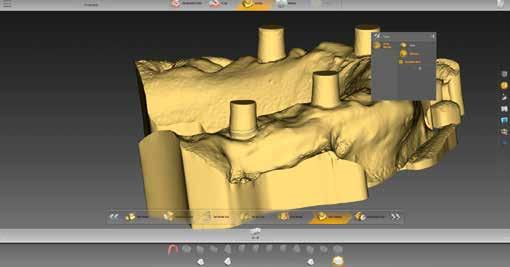

3–4. ábrák: Ellenőrizzük az érintkezési pontok egyensúlyát.

szükséges információ rögzítésére megfelelt. A meglévő pótlásról is készült egy ún. BioCopy-Scan (1. ábra), amelyet összevetíthetünk a felső állcsontról készült, az adhezív sapkákat is tartalmazó beolvasással (Atlantis Conus Abutment, Dentsply Sirona). Így meghatározhattuk a vesztibuláris szituációt és a vertikális helyzetet, ami megkönnyíti a funkcionális és esztétikai szempontból is kiemelkedő munka elkészítését. Ellenőriztük a meglévő pótlás egyensúlyát és érintkezési pontjait (3–4. ábrák), meghatároztuk a minta tengelyét (5. ábra), majd az adatokat az inLab szoftverbe importáltuk.

7. ábra: A maxilla mintája.